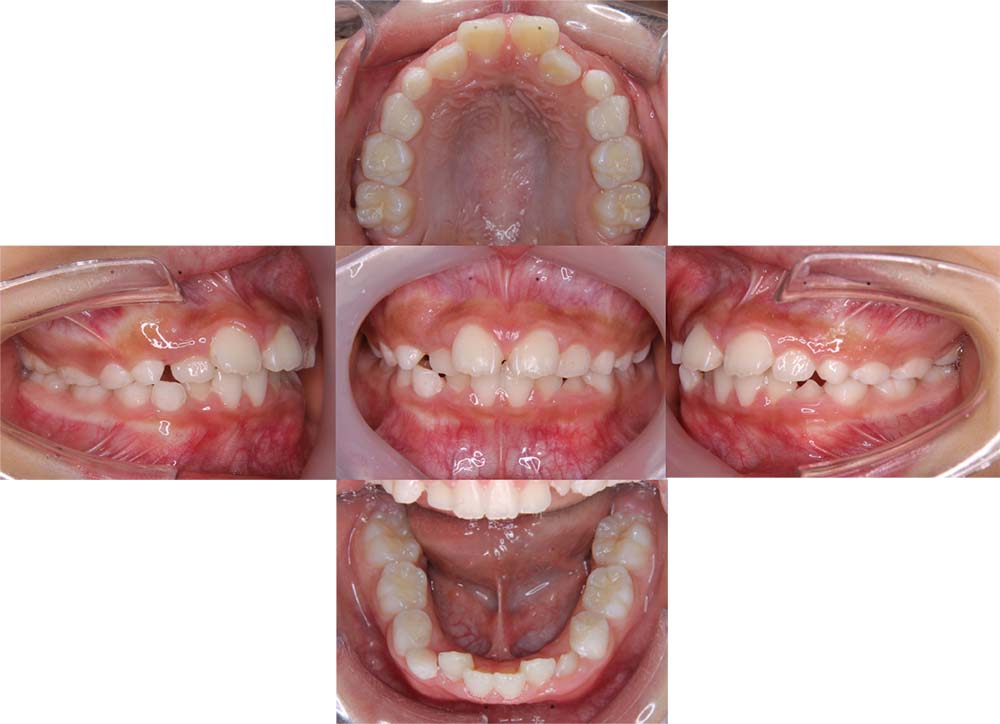

症例02

| 主訴 | 下あご顎が出ている。曲がっている。 |

| 診断名あるいは主な症状 | 反対咬合、非対称、空隙歯列、過蓋咬合 |

| 年齢/性別 | 19歳・女性 |

| 矯正ステージ | 大人の矯正治療 |

| 治療方法 | ワイヤー矯正、顎矯正手術の施行 |

| 抜歯部位/抜歯有無 | 非抜歯 |

| 治療内容 | 上下顎歯列を並べた後に顎矯正手術の施行。 |

| 費用 | 保険治療 |

| 治療期間 | 3年2ヶ月 |

| 主なリスク・副作用 | 痛み、歯根吸収、歯肉退縮、虫歯、後戻り |